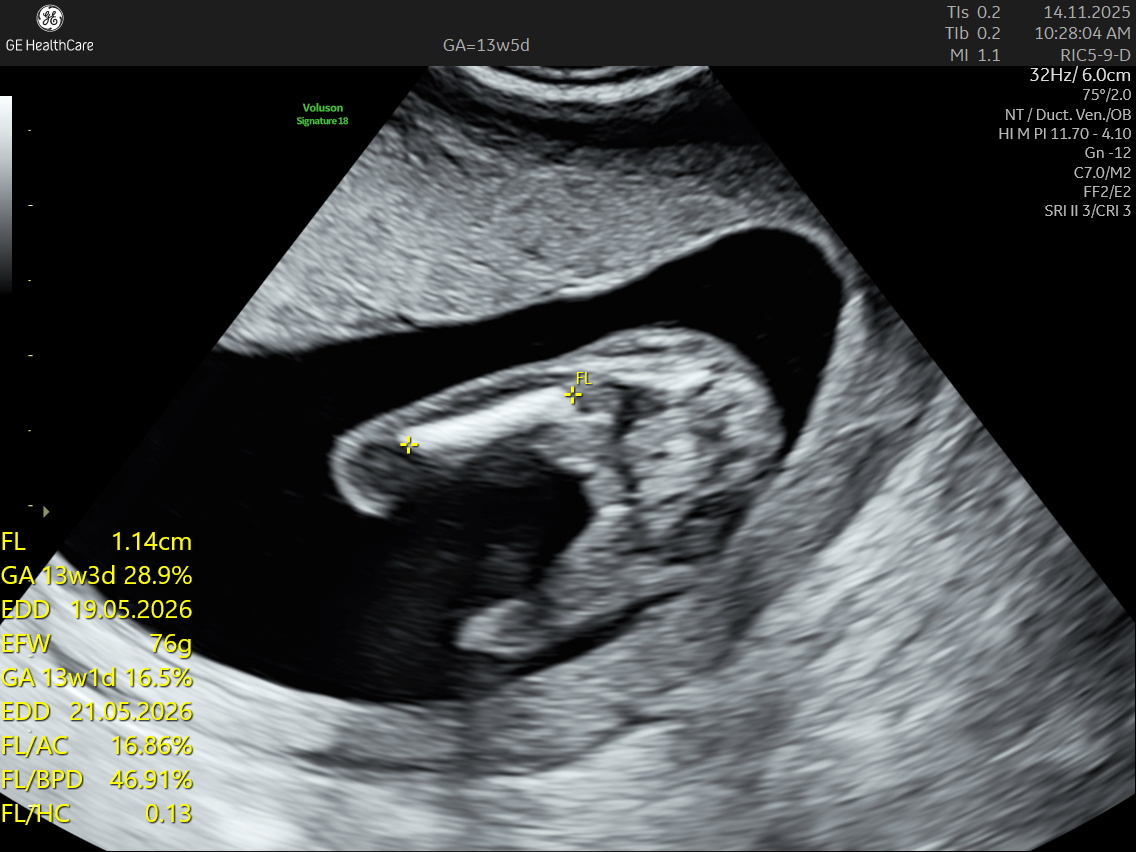

The NT scan is a non-invasive ultrasound examination conducted in the first trimester (12–13 weeks). It measures the nuchal translucency (the fluid at the back of the fetus’s neck) and combines it with the maternal blood test for a detailed risk profile. NT Scan is an important early screening test for Down syndrome (Trisomy 21), Edwards syndrome (Trisomy 18), and Patau syndrome (Trisomy 13).

Although the NT scan is mainly a screening tool and not diagnostic on its own, it can identify about 50% of major fetal abnormalities when combined with other assessments like blood tests and detailed ultrasound. The scan also helps to screen some basic anatomical structures during the first trimester, especially the fetal heart anatomy, brain, face, spine, stomach, abdominal wall, kidneys, bladder, and extremities to varying degrees depending on gestational age and maternal factors.